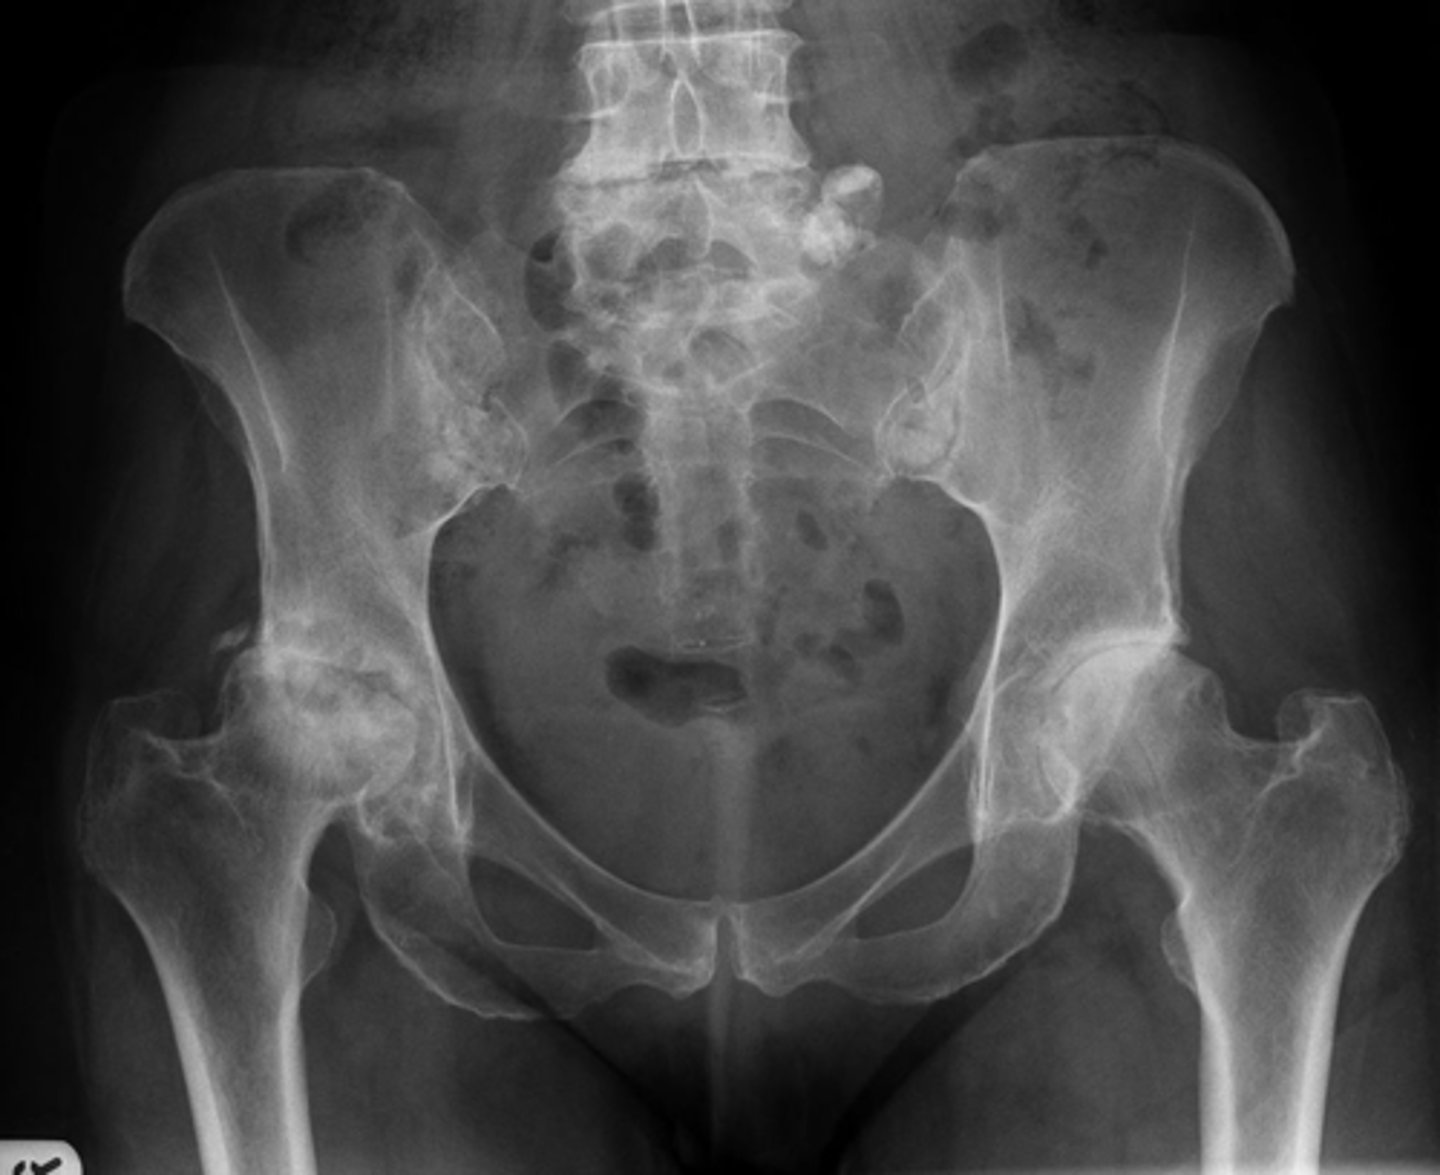

Right hip

Bone

Right femoroacetabular joint

Joint

Yes

Joint space narrowed?

Non-uniform

Uniform/non-uniform narrowing

No

Periarticular erosions

Osteophytes

Subchondral cysts

Subchondral sclerosis

Periarticular osteopenia

Soft tissue swelling

Intra-articular calcification

Joint ankylosis

Extra-articular calcification/osseous bodies

Subluxation

Dislocation/diastasis

Bilateral

Bilateral/unilateral

Degenerative

Category of joint disease

Osteoarthrosis

Most likely diagnosis?

Orthopedic referral

Next step?

- Collapse

- Step-off deformity

- More fragmentation

How can you differentiate this from avascular necrosis?